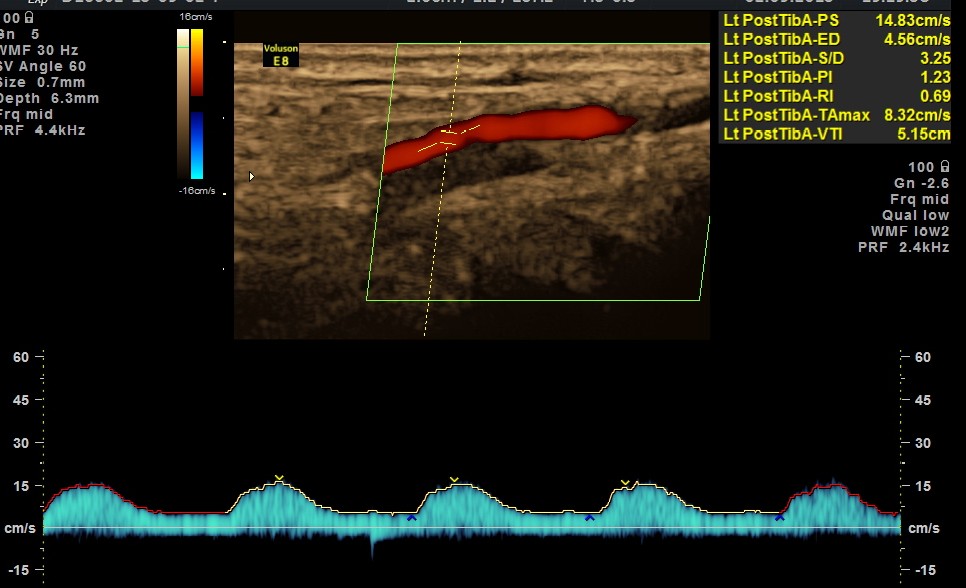

The following pictures were obtained .

BOTH DORSALIS PEDIS ARTERIES SHOW LOSS OF ARTERIAL TONE AND MONOPHASIC FLOW.

EXTENSIVE ATHEROSCLEROTIC OBSTRUCTIVE DISEASE OF THE LOWER LIMB ARTERIES WAS SEEN WITH THE CHANGES IN THE RIGHT COMMON FEMORAL ARTERY BEING MORE THAN THE LEFT CFA.